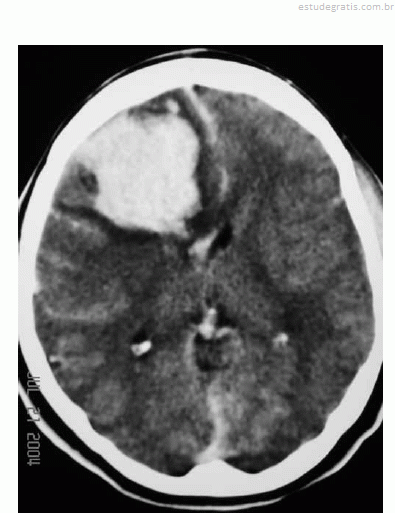

Uma mulher de 29 anos de idade teve sua gestação interrompida com 35 semanas, mediante parto cesariano, por ter apresentado quadro compatível com a doença hipertensiva específica da gravidez. No quinto dia de pós-operatório, apresentou importante dor de cabeça seguida de crises convulsivas; na avaliação laboratorial, foram atestadas plaquetopenia e alteração da função hepática. Ela foi levada à unidade de terapia intensiva, onde o plantonista observou hemiparesia esquerda e solicitou uma tomografia de crânio sem contraste, que é reproduzida abaixo.

Com base nessas informações, julgue os itens que se seguem.